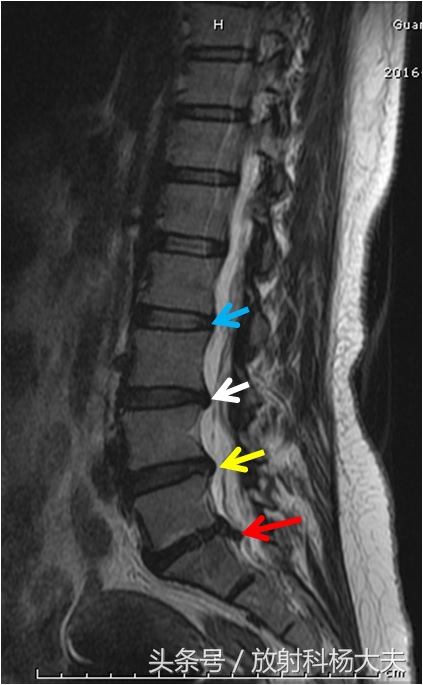

放射科大夫经常在一个病人身上,看到三种不同的表现,比如下图为一老人的腰椎MRI,从上往下,不同的标示,分别代表正常椎间盘,椎间盘膨出,椎间盘突出和椎间盘脱出。注意,影像报告上只诊断具体类型,而不诊断“椎间盘突出症”,少了一个“症”字,其中的内涵,就代表放射科和骨科的差距。